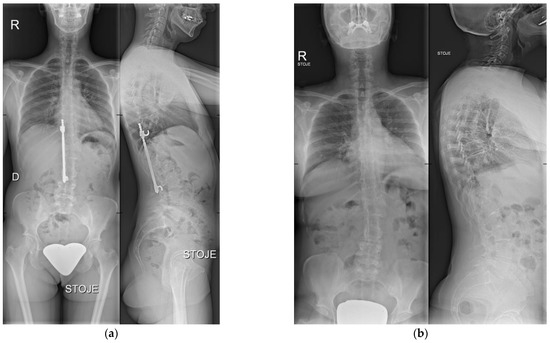

We performed a retrospective, institutional review board-approved (No. 2/2022) analysis of a single-institution case series of 12 consecutive patients with adolescent idiopathic scoliosis, treated primarily with surgical correction using HR instrumentation (Figure 1a) between 1982 and 1997, and afterward with watchful waiting of residual spinal deformity after HR instrumentation removal (Figure 1b), whereby no patient consented to surgical residual deformity correction. Written informed consent from the patients was obtained.

Figure 1. (a) X-ray taken before HR instrumentation removal. Anteroposterior (left) and lateral (right) view. (b) Most recent X-ray after HR instrumentation removal. Anteroposterior (left) and lateral (right) view.

This study aimed to assess long-term radiological outcomes in patients from our institution who were treated primarily for adolescent idiopathic scoliosis with surgical correction using HR instrumentation (Figure 1a), and afterward with watchful waiting of residual spinal deformity after HR instrumentation removal, whereby no patient consented to adult spinal deformity correction (Figure 1b). The results showed no significant radiological signs of ASD progression after an average follow-up of 11 years after the HR instrumentation removal.